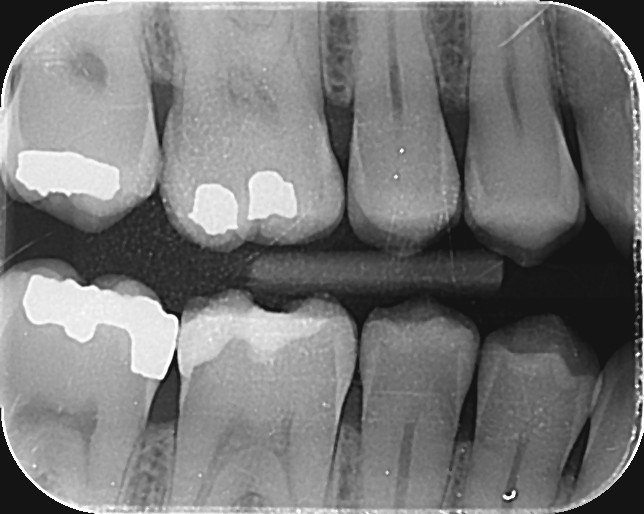

14. Which surfaces shows recurrent caries?

15. Which surface shows recurrent caries?

38. Which surfaces shows recurrent caries?

40. Which surfaces shows recurrent caries?

42. Which surfaces shows recurrent caries?

43. Which surface shows recurrent caries?

45. Which surface shows recurrent caries?

46. Which teeth shows recurrent caries?

47. Which surface(s) shows recurrent caries?

50. Which surface(s) shows recurrent caries?